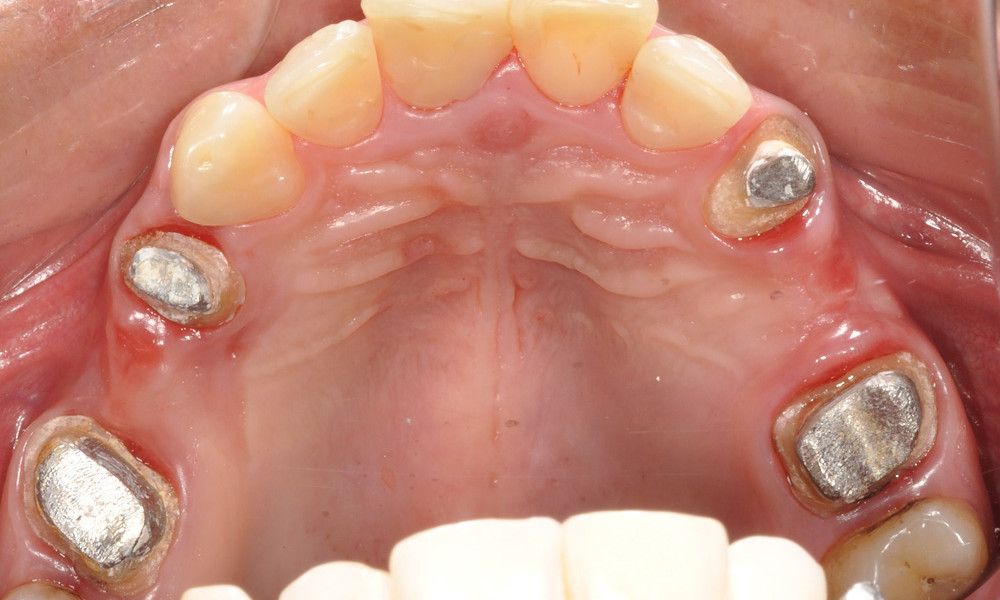

Reporte del Caso: Paciente sexo masculino, 36 años, con diagnóstico de esquizofrenia y trastorno bipolar en tratamiento. Consulta por el recambio de dos prótesis fijas plurales (PFP) de reemplazo de dientes 4 y 13 con pilares en piezas 3, 5, 12 y 14 mediante rehabilitaciones unitarias de los dientes pilares y reemplazo mediante implantes en zonas edéntulas.

El estudio imagenológico evidencia una pérdida ósea severa en altitud y grosor, situación que complejiza la colocación de un implante. Se analizan alternativas de tratamiento y se opta por una vestibuloplastía mediante autoinjerto conectivo de mucosa palatina que se reposiciona sobre la zona del defecto óseo. Además se realiza retratamiento de ambas PFP, ahora en zirconia, por motivos estéticos y oclusales. Se realizan controles posteriores para evaluar la respuesta gingival a la vestibuloplastía.